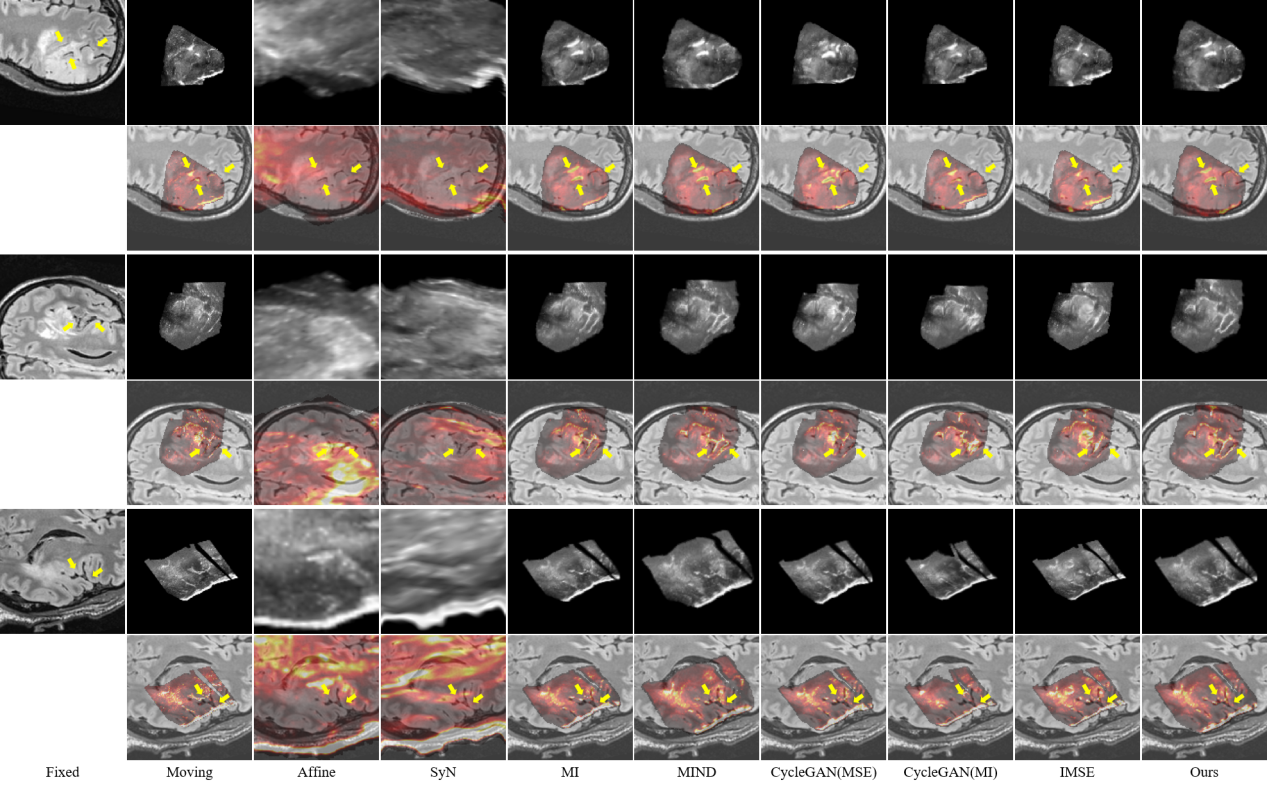

研究结果表明,SynMSE 在L2R 2022 CT-MR腹部数据集、临床宫颈CT-MR数据集以及CuRIOUS MR-US脑数据集上均取得了最优配准性能。与传统方法相比,SynMSE显著提升了Dice系数、降低了HD95与TRE误差,实现了在复杂模态差异下的高精度解剖结构对齐。图4-图6分别为所提出方法在三个数据集上的定性结果展示,红色标注代表固定图像的目标器官区域,黄色标注代表浮动图像与配准后图像的目标器官区域。表示图中结果显示,SynMSE更好的克服了多模态图像间的复杂分布差异,不仅实现了更精确的配准效果,而且有效保持了组织边界与解剖拓扑的完整性,明显优于现有方法。

图6:所提出方法与现有方法在CuRIOUS MR-US脑数据集上的定性效果(黄色箭头指向图像上的较为明显的脑沟等显著结构)